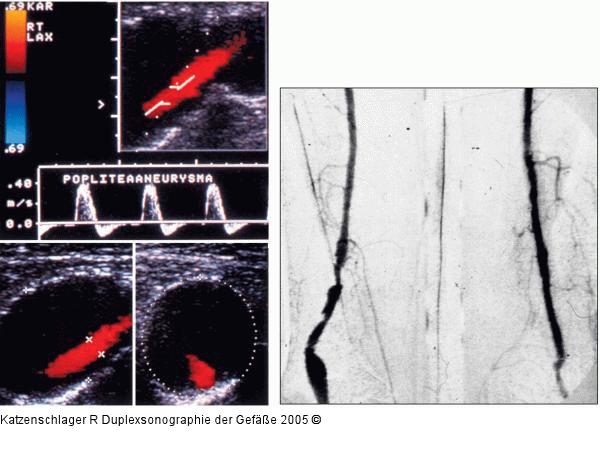

Abbildung 15: Duplexsonographie - A. poplitea - Aneurysma Aneurysma der A. poplitea mit wandständigem Thrombus |

Aneurysma der A. poplitea mit wandständigem Thrombus |